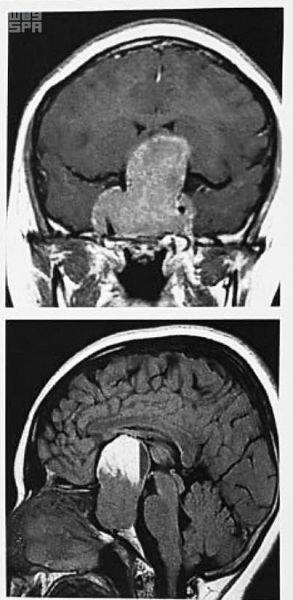

نجح فريق مختص من مركز العلوم العصبية بمدينة الملك عبد الله الطبية بمكة المكرمة، اليوم الأربعاء، في استعادة فتاة مصرية بصرها كانت قد قدمت مع والديها لأداء فريضة الحج هذا الموسم. وبعد 7 ساعات متواصلة، أنهى الفريق الطبي المختص العملية الجراحية بقاع الجمجمة للفتاة "16 عاماً"، حيث تم استئصال ورم نازف في الغدة النخامية كان ضاغطاً على عصب العين عبر منظار بفتحة بالأنف حجمه ١ سم.

وكانت الفتاة المصرية قد أُحيلت للمركز، وذلك بعد تشخيص حالتها بفقدان شبه كامل للإبصار في العين اليسرى وضعف شديد في العين اليمنى بسبب وجود ورم ضخم ونازف في الدماغ في الغدة النخامية.